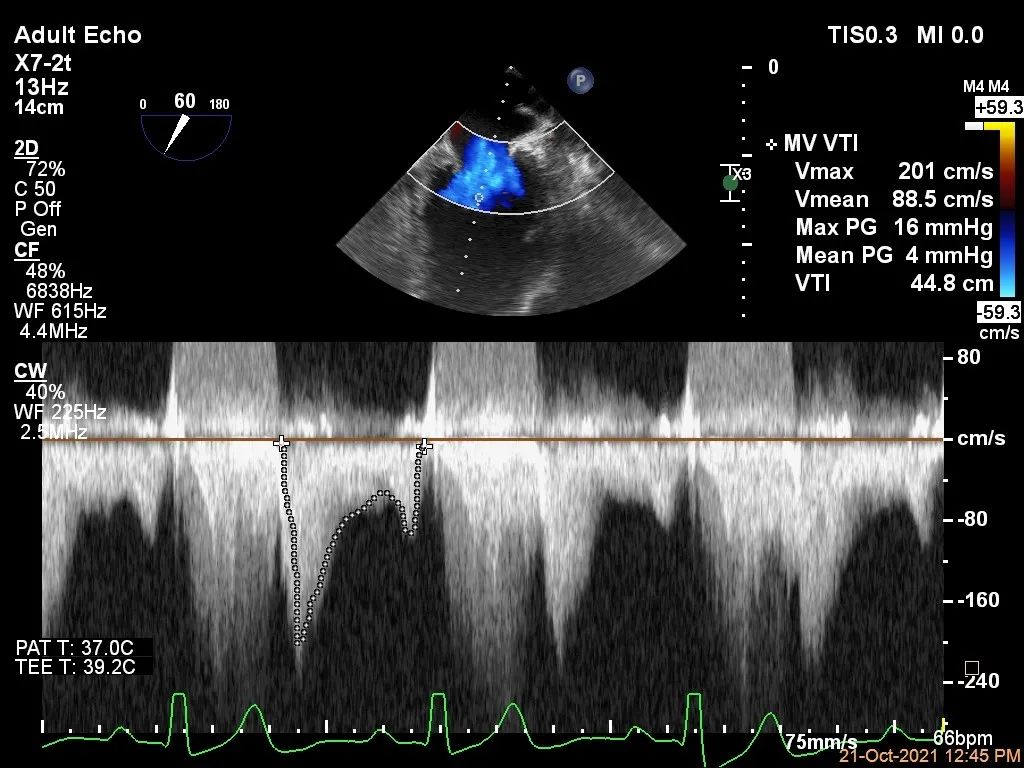

Bicom:MR(重度),反流束宽22mm,反流面积24.2cm²,PISA法定量EROA:2.3cm²,Rvol:274ml,RF:57%,r:16mm。

二尖瓣反流频谱呈全收缩期

肺静脉血流频谱呈收缩期反向

二尖瓣口平均跨瓣压差:4mmHg

第一个夹子放置侯二尖瓣口平均跨瓣压差:4mmHg

第二个夹子放置侯二尖瓣口平均跨瓣压差:4mmHg